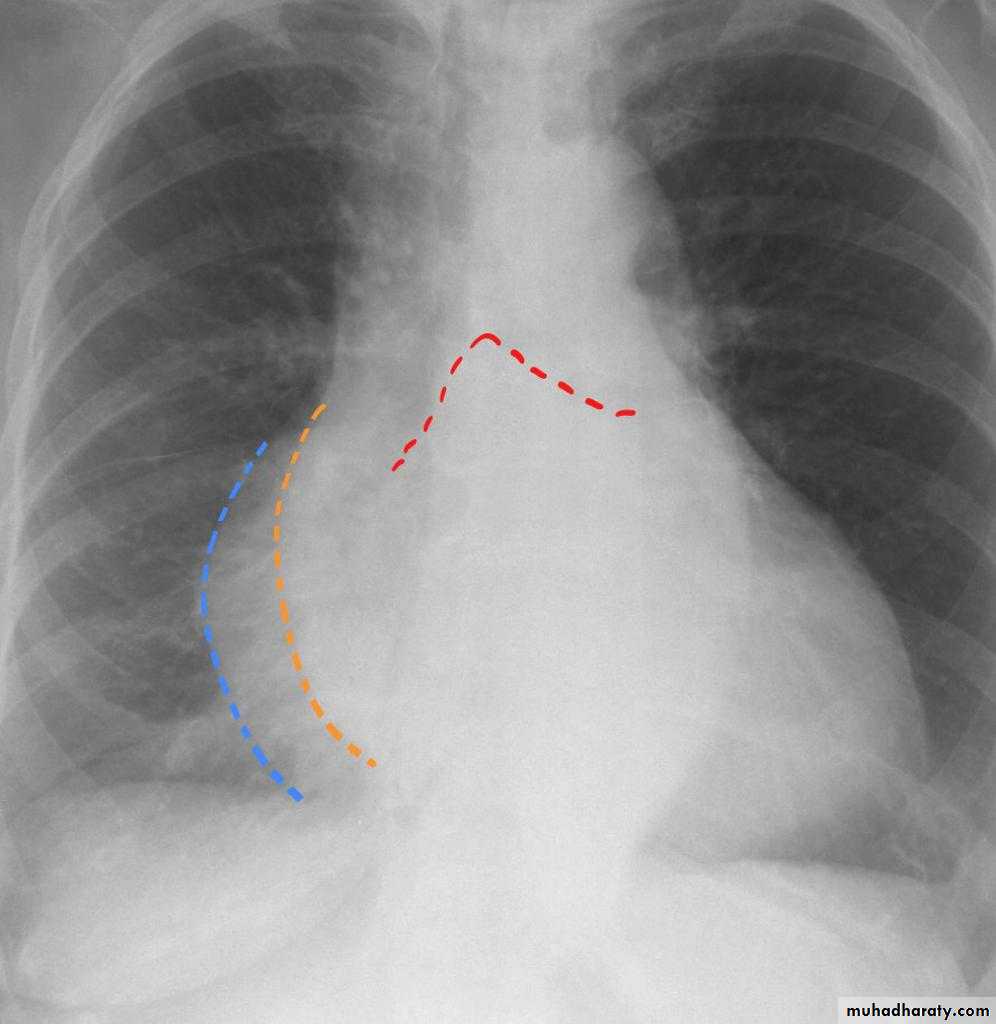

Mitral valve disease

Mitral valve disease (double density RT cardiac border)

15.mitral valve disease & their sign

16.MVD